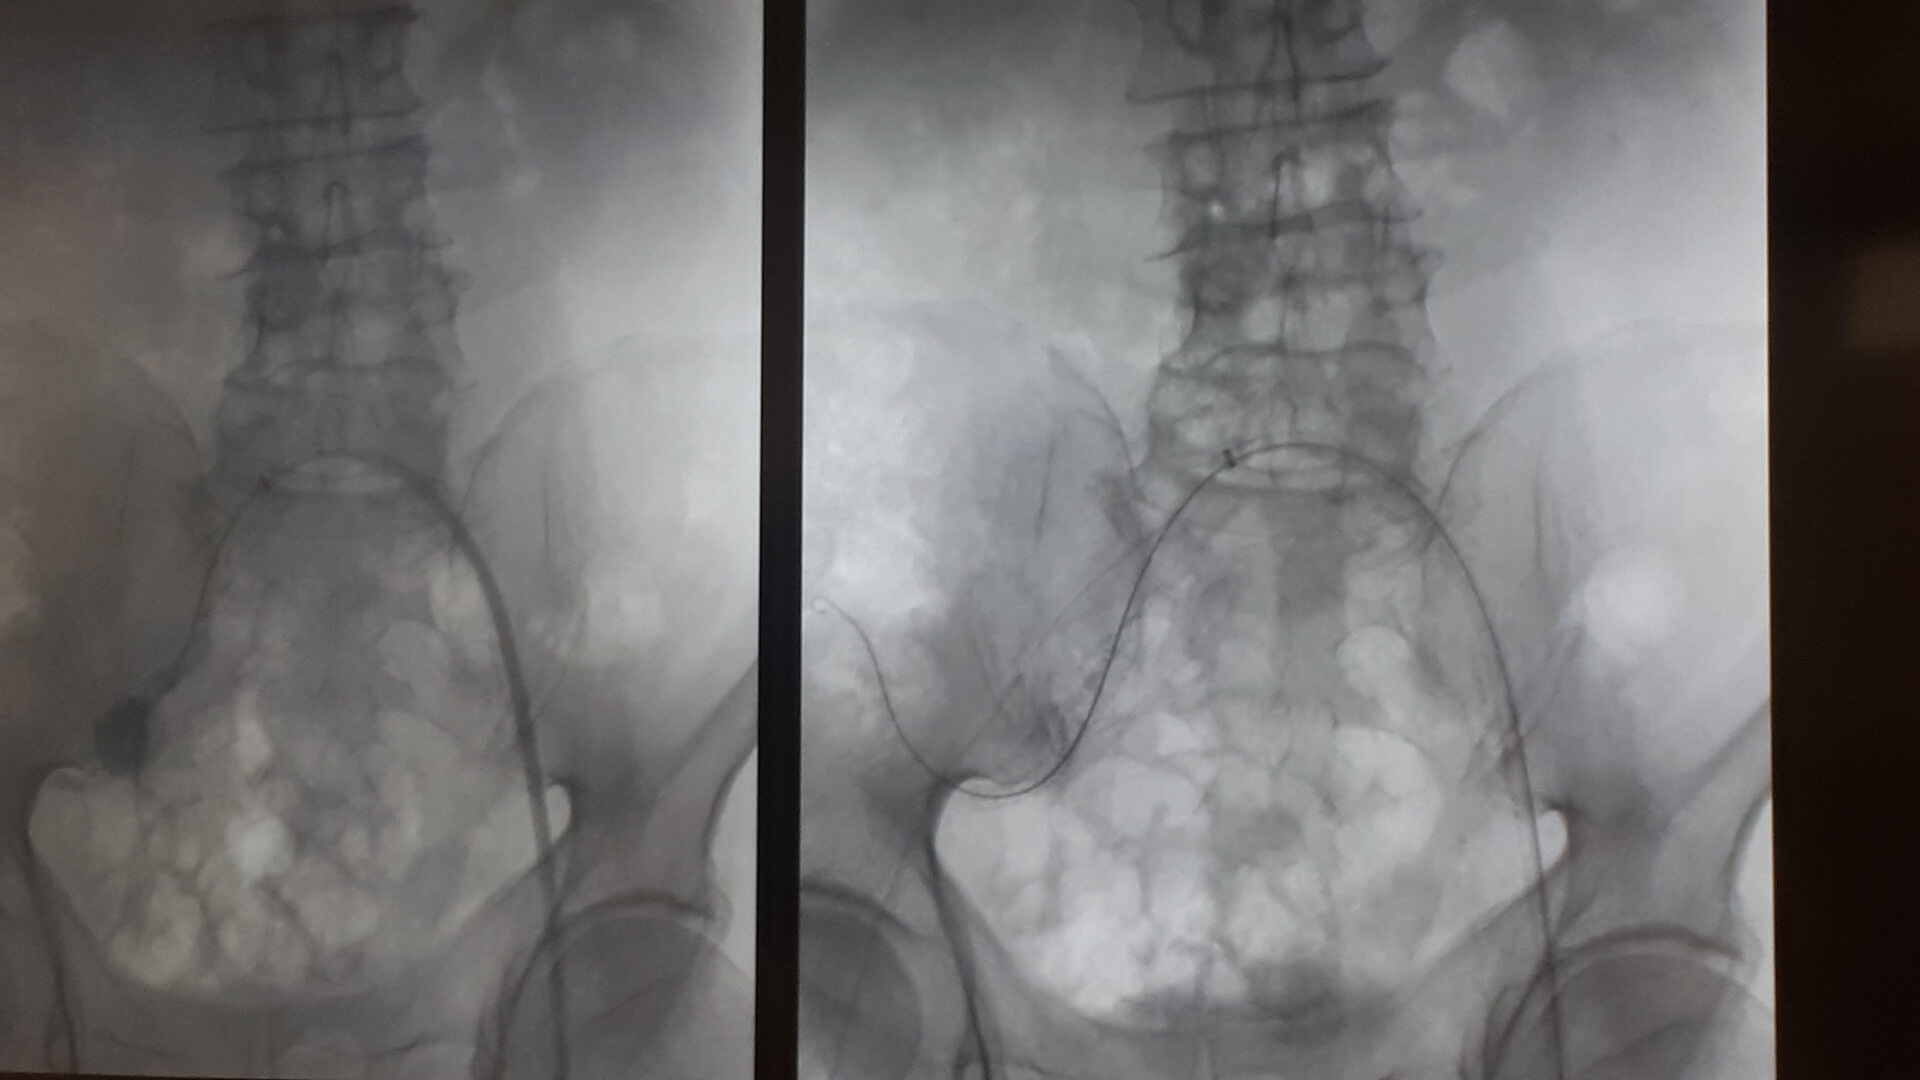

Pierwszą w Polsce operację wszczepienia nowego rodzaju stentgraftu, czyli specjalnej protezy do zabezpieczania tętniaków aorty, przeprowadzili lekarze z Uniwersyteckiego Szpitala Klinicznego w Białymstoku.

Chodziło o tętniaka tętnicy biodrowej u 64-letniego pacjenta. Operację przeprowadzono w minioną środę (10.04) w Klinice Chirurgii Naczyń i Transplantacji USK. Pacjent czuje się dobrze i niedługo wychodzi ze szpitala.

Jak mówił w czwartek (11.04) na konferencji prasowej kierownik tej kliniki dr hab. Jerzy Głowiński, tętniak miał prawie 4 cm, co w relacji do wielkości tętnicy biodrowej wewnętrznej stanowiło duże zagrożenie, bo w każdej chwili ścianki naczynia krwionośnego mogły pęknąć, powodując – zagrażający życiu – krwotok wewnętrzny. - Możliwości uratowania byłyby naprawdę znikome – powiedział.

W przypadku tego chorego nie wchodziła w grę klasyczna operacja, bo tętniak znajdował się zbyt głęboko, by był możliwy do niego dostęp chirurgiczny. Dotąd zasadą postępowania w takiej sytuacji było podwiązywanie lub wyłączanie tętnicy (klejem lub specjalnymi spiralami). Dr Głowiński zwrócił uwagę, że choć ta tętnica nie ratuje życia, to poprawia komfort pacjenta, bo odpowiada za ukrwienie narządów jamy brzusznej oraz – co istotne jest u mężczyzn – za prawidłową erekcję.

Rozwiązaniem okazał się nowy rodzaj stentgraftu, czyli specjalnej protezy wszczepianej do tętnic. "Jest to stentgraft, który jest jednocześnie i miękki, i na tyle sztywny, że się do tego celu dobrze nadawał" – powiedział. Zwrócił przy tym uwagę, że stosowane już standardowo stentgrafty są albo sztywne, albo elastyczne i do zabezpieczenia tętniaka w takim miejscu się nie nadawały.

DrJerzy Głowiński wyjaśniał, że tętnica biodrowa jest stosunkowo mała i kręta, do tego jej średnica nie jest na całej długości taka sama. Nowy rodzaj stentgraftu składającego się z pierścieni naprzemiennie sztywnych i elastycznych dał możliwość "domodelowania" go w taki sposób, by na całym zabezpieczanym tętnicy odcinku był właściwie zainstalowany.

Do tego od wewnątrz stentgraft jest pokryty heparyną, co ma zapewnić jego długotrwałą drożność i zapobieganie zakrzepicy. - Zakładamy, że stentgraft posłuży pacjentowi również na długie lata – dodał kierownik Kliniki Chirurgii Naczyń i Transplantacji USK w Białymstoku. Przyznał, że takie umiejscowienie tętniaka jest rzadkie, w statystykach białostockiej kliniki trafia się 2-3 razy do roku. Zoperowany z użyciem nowego rodzaju stentgraftu pacjent czekał na to dwa miesiące. Sama proteza kosztuje ok. 9-10 tys. zł. Stosowane dotąd inne ich rodzaje są średnio dwa razy tańsze.